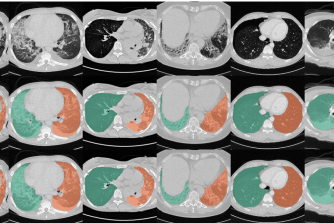

Lung imaging

We are investigating machine learning approaches to analyse lung imaging data ranging from prediction models to unsupervised techniques to identify phenotypes in large scale populations.